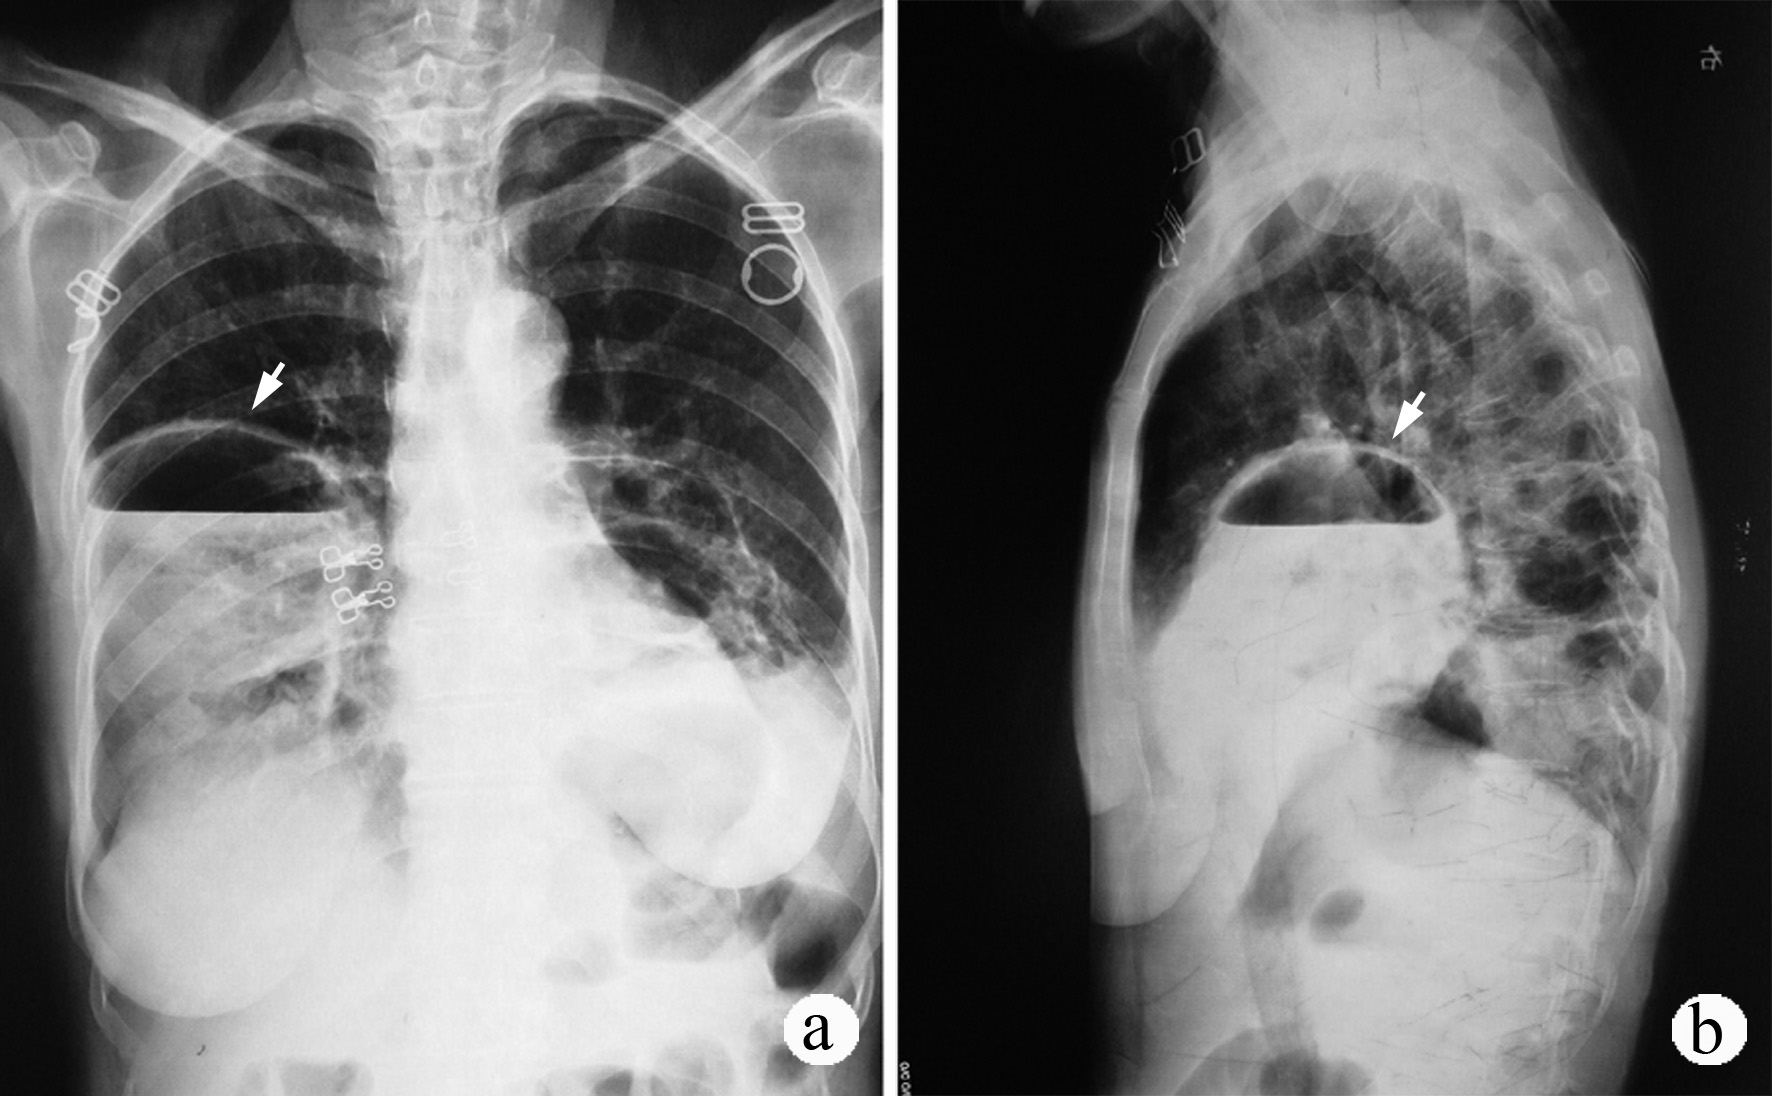

五、肺部慢性感染 如肺结核、支气管扩张症等患者,支气管上皮在慢性感染过程中可能化生为鳞状上皮,终致癌变,但这类情况较为少见。

先生性支气管肺囊肿